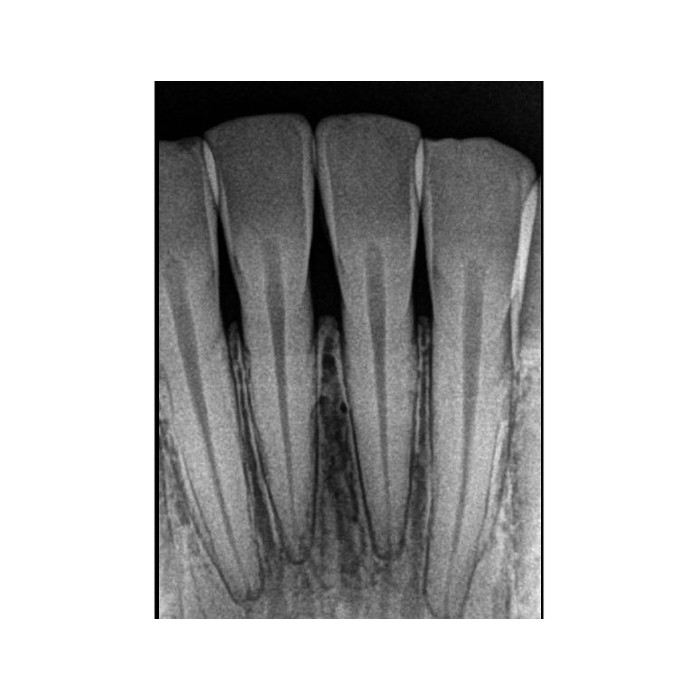

Ключевое преимущество RVG 5200 — высокая разрешающая способность 16 пар линий/мм. Это означает исключительную детализацию снимка, позволяющую четко визуализировать анатомические структуры, тонкие корневые каналы, начальные стадии кариеса и минимальные изменения в периапикальных тканях. Ваша диагностика становится более точной и уверенной.

В чем разница между 16 пар/мм и другими показателями разрешения?

Разрешение в парах линий на миллиметр (пл/мм) — это объективный параметр, характеризующий способность системы различать мелкие детали. Показатель 16 пл/мм является высоким и обеспечивает отличную диагностическую информативность снимков, необходимую для эндодонтии, пародонтологии и выявления скрытого кариеса.